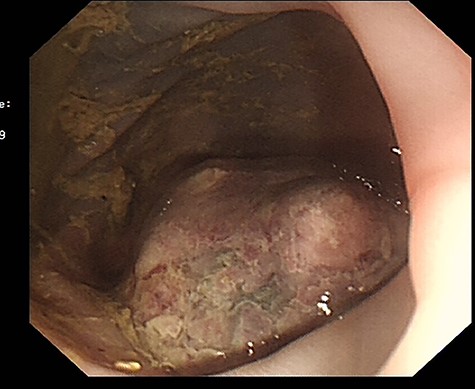

The patient’s obstructive symptoms resolved following administration of adequate analgesia and anti-spasmodic medication (Hyoscine). As she remained stable with no biochemical finding or radiologic features suggestive of ischemia or impending perforation, an urgent flexible sigmoidoscopy was arranged which showed a large mid-descending submucosal colonic mass with a smooth surface and mucosal ulceration, confirming the radiological impression of a submucosal lipoma (Fig. 2).